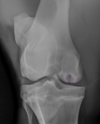

What is shown in these images?

A

Left: osteochondrosis of lateral trochlear ridge of talus

-“missing” bone that is cartilaginous instead of mineralized

Right: osteochondrosis of lateral trochlear ridge of talus

-lesion is the divot seen on lateral trochlear ridge

-red arrow is pointing to normal variation of the medial trochlear ridge